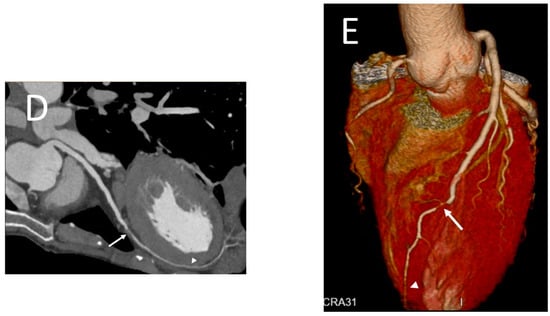

- Tweet, M.S.; Akhtar, N.J.; Hayes, S.N.; Best, P.J.; Gulati, R.; Araoz, P.A. Spontaneous coronary artery dissection: Acute findings on coronary computed tomography angiography. Eur. Heart J. Acute Cardiovasc. Care 2019, 8, 467–475. [Google Scholar] [CrossRef]

- Tweet, M.S.; Gulati, R.; Williamson, E.E.; Vrtiska, T.J.; Hayes, S.N. Multimodality Imaging for Spontaneous Coronary Artery Dissection in Women. JACC Cardiovasc. Imaging 2016, 9, 436–450. [Google Scholar] [CrossRef]